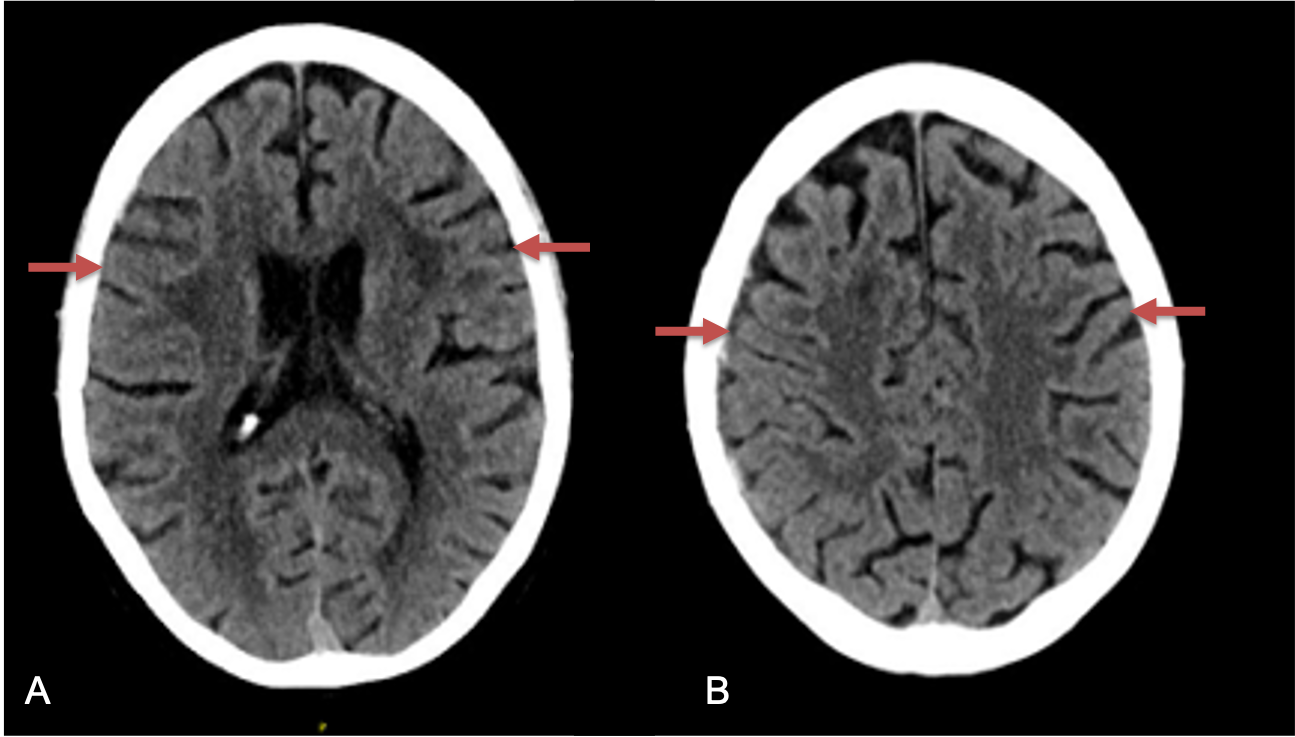

Figure 1. A) 6 weeks post mild trauma B) 4 weeks post mild trauma demonstrate stable subacute subdural collections with mild growth and sulcal effacement.

A man in his 80s developed mild dizziness and headache following incidental trauma working in his garage one day. He presented several weeks later to the ER and was diagnosed with bilateral subdural hematomas, which were initially managed with observation, low dose Decadron, considering the mildness of symptoms, advanced age, and history of CLL with thrombocyptopenia (<100k). Over the next 4 weeks, the collections remained relatively stable with evidence of slight growth (10 to 12 mm thickness, and 2 mm right to left shift) on NCT (Figure 1. A and B).